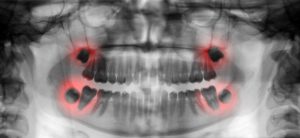

Teeth X-ray

At Robert Stoner Orthodontics, our orthodontic treatments are performed with leading-edge technology. Afterwards, we will take a panoramic x-ray to see the location of your wisdom teeth and find out if full extraction is needed. If extraction is necessary, we recommend removing the wisdom teeth before the roots settle in. This way, we can pop out the tooth bud in a manner that is much easier for our patients.